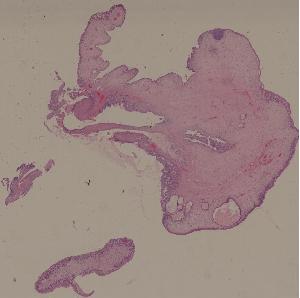

28.结肠腺瘤